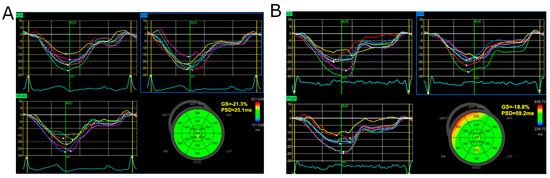

2.2. Global Longitudinal Strain and Myocardial Work Analysis

| Entire Group (n = 97) | Normal Levels of Troponin I (n = 57) | Increased Level of Troponin I (n = 37) | p Value | |

|---|---|---|---|---|

| GLS (%) | −19.0 (−20.0–−17.0) | −19.0 (−21.0–−18.0) | −18.0 (−19.0–−16.0) | 0.008 |

| PSD (ms) | 45 (39–56) | 43 (36–49) | 54 (43–64) | <0.001 |

| GWI (mmHg%) | 1834 (1168–2054) | 1857 (1867–2045) | 1867 (1641–2060) | 0.53 |

| GCW (mmHg%) | 2130 (2010–2398) | 2120 (1976–2035) | 2182 (2030–2460) | 0.67 |

| GWW (mmHg%) | 119 (78–175) | 97 (69–132) | 168 (121–196) | <0.005 |

| GWE (%) | 94 (92–96) | 95 (94–96) | 93 (90–94) | <0.005 |